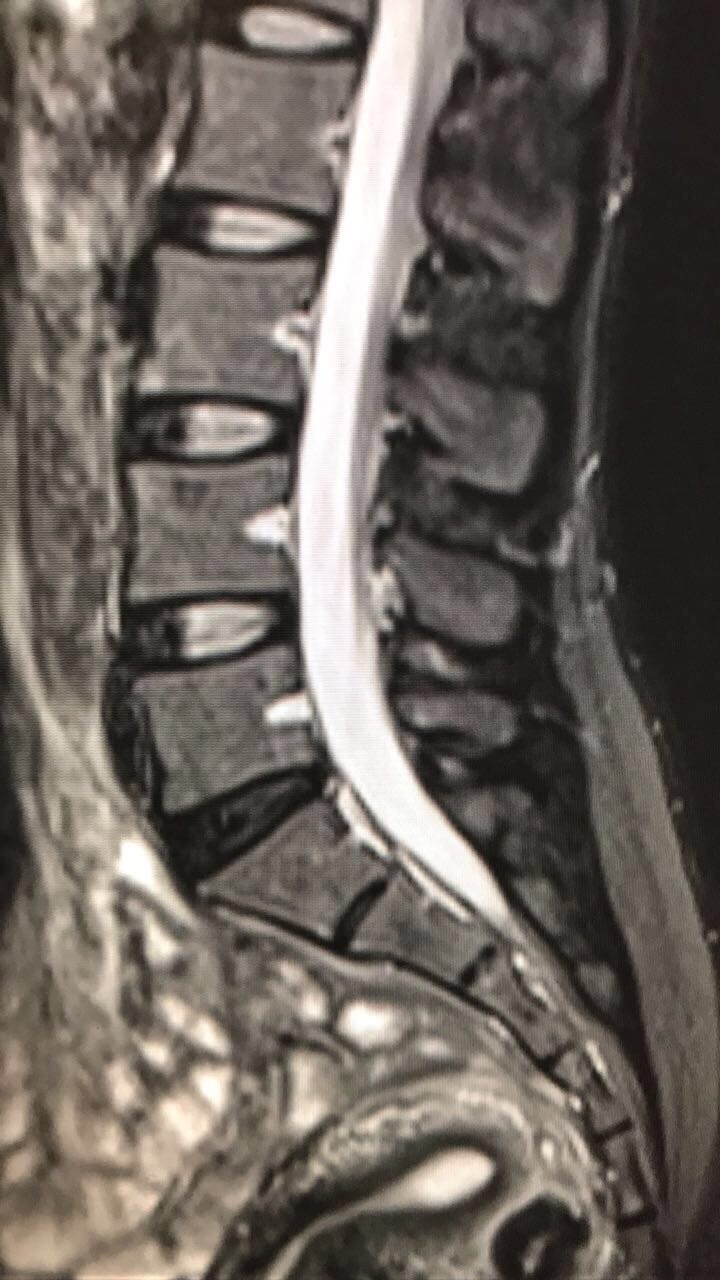

From www.chennaispinecare.com